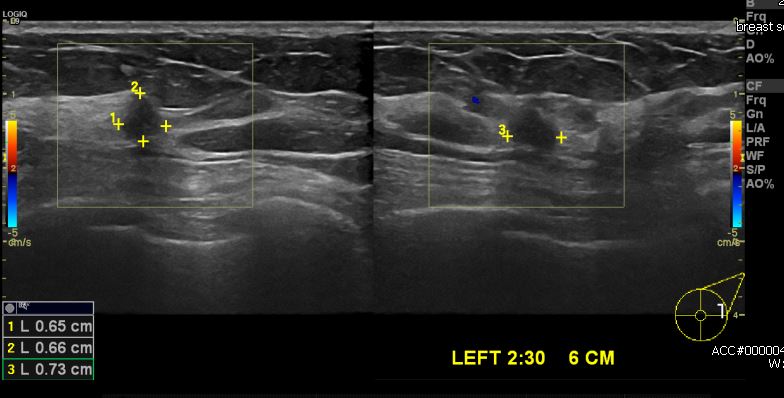

건강 검진상 이상 소견으로 내원하신 50대 여성분으로  본원 초음파 시행 후 좌측

2시 30분 방향에 6 cm의 의심 스러운 혹 중앙 핵 생검 시행하여 좌측 침윤성 유관암

진단 되었습니다.